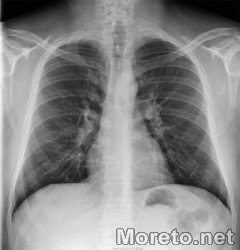

Муковисцидоза

Целта на събитието е да привлече вниманието на обществото към проблемите на болните от муковисцидоза, при които дишането е затруднено. То поставя началото на кампания за събиране на средства за ремонт на 2 стаи в УМБАЛ "Св.Марина", в които да се лекуват пациентите със заболяването.

Организатор е Асоциация "Муковисцидоза", по повод Световния ден на муковисцидозата 21 ноември, който се отбелязва за пети път у нас. Събития по повода ще се проведат в София и Варна, под мотото "За мечтите и надеждите".